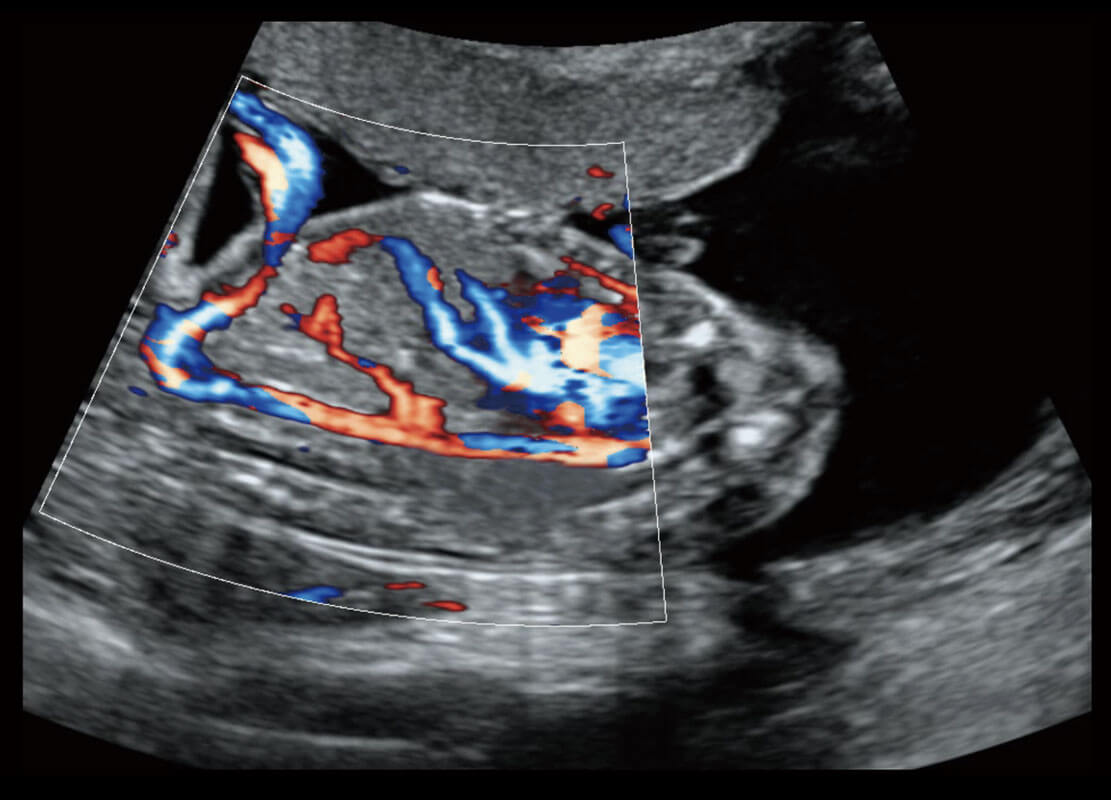

P60优异的图像质量搭载专科探头,在妇科基础疾病的诊断、卵泡生长的监测、输卵管通畅情况的判别等方面为您提供生殖应用方案。

腔内妇科-卵巢